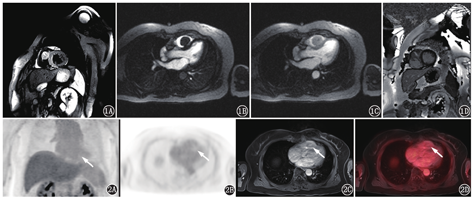

患者女,68岁,因"体格检查发现右心室肿物1个月"入院。患者1个月前体格检查时超声心动图提示:右心室腔内大小约26 mm×26 mm等回声团块,附着于右心室体部,致右心室流出道梗阻。患者诉平日胸闷憋气症状不明显。入院体格检查:体温36.1 ℃,心率:75次/min,呼吸:18次/min,血压:127/75 mmHg(1 mmHg=0.133 kPa)。实验室检查:血常规、肝肾功能、肿瘤标志物[包括癌胚抗原、甲胎蛋白、糖类抗原(carbohydrate antigen, CA)125、CA19-9、CA72-4、细胞角蛋白19片段抗原、神经元特异性烯醇化酶、鳞状细胞癌相关抗原、人绒毛膜促性腺激素、降钙素]均在正常范围。心电图示:窦性心律,完全性右束支阻滞,心电图不正常T波。胸部平扫CT示右心室内团块状高密度,平扫CT值50.4 HU(心腔内血池平扫CT值25.3 HU)。为了解病变代谢情况、明确病变良恶性及病变与周围结构毗邻关系,行心脏18F-脱氧葡萄糖(fluorodeoxyglucose, FDG;本科室加速器生产) PET/MR(德国Siemens Biograph mMR)检查。患者禁食16 h,测空腹血糖为4.5 mmol/L,静脉注射18F-FDG 310.8 MBq后40 min行心脏PET/MR显像:同步行PET及人体轴位MR采集[PET采用列表(list)模式,人体横轴位MR包括T1加权( weighted, T1W)及T2W序列采集],再行心脏轴位(心脏短轴及2、3、4腔心脏长轴)MR采集,包括电影序列、T2黑血序列、首次血流灌注动态成像及延迟增强序列。心脏电影成像示右心室心腔内大小约30 mm×23 mm结节状充盈缺损,病变附着于室间隔,随心肌舒缩而同步运动。T2黑血序列示病变呈稍长T2信号,信号稍欠均匀(图1A),首次血流灌注动态成像示病变高灌注(图1B,图1C),病变延迟强化(图1D)。18F-FDG显像示心肌代谢抑制良好,右心室心腔内病变轻微代谢,同心腔内血池(图2)。PET/MR结果示右心室心腔内病变为良性可能性大。后患者行右心室肿物切除、三尖瓣成形术。术中探查发现肿瘤瘤体附着于右心室游离壁及室间隔,瘤体完整有包膜,予以切除。术后病理示(右心室肿物)心肌间可见甲状腺滤泡性肿瘤结节,结合形态及免疫组织化学结果,首先考虑甲状腺滤泡癌转移,建议结合甲状腺部位检查情况,并除外其他少见情况(如甲状腺组织异位等;图3)。免疫组织化学结果:细胞角蛋白(cytokeratin, CK;+),CK19(少数+),细胞增殖核抗原Ki-67(+1%),甲状腺转录因子-1(thyroid transcription factor-1, TTF-1;+),成对框基因8编码的转录因子(paired box gene 8, PAX-8; +),甲状腺球蛋白(thyroglobulin, Tg; +)。患者后又行超声检查,结果示甲状腺超声未见明显异常。心外科与病理科再次会诊后,考虑为右心室异位甲状腺。

心脏肿瘤少见,可分为原发性和继发性2种,后者的发病率是前者的20~40倍[1]。MR在心脏肿瘤的诊断中发挥了重要作用[1,2,3]。MR可准确、全面、清楚地显示心脏肿瘤的部位、大小、形态、与周围结构的关系等,且特定的组织信号特征定性诊断脂肪瘤及纤维瘤的准确性非常高,但该方法对于大多数心脏肿瘤的良恶性鉴别主要根据病变的生长方式、血供特点等,缺乏特异性[2]。18F-FDG PET反映病变的糖代谢,有助于心脏肿瘤的良恶性鉴别。一体化PET/MR融合了PET与MR技术,能提供一站式解剖结构及代谢信息,对于心脏肿瘤的良恶性鉴别及治疗方案的制定具有重要意义[4]。本例为甲状腺异位于右心室患者,18F-FDG PET/MR在其诊断中发挥了重要作用。MR清晰显示病变位于右心室,高灌注提示富血供病变,并有延迟强化,提示其为肿瘤性病变而非血栓;病变局限于右心室,形态较规则,体积较小,未呈浸润性生长,且核磁信号相对均匀,提示为良性病变。而18F-FDG PET显示病变轻微代谢,最大标准摄取值(maximam standardized uptake value, SUVmax)为1.5,与血池及心室壁心肌相仿(心肌SUVmax为1.6),进一步验证了其为良性肿瘤性病变。

心脏内异位甲状腺非常罕见,文献多为个案报道[6,7,8,9,10]。异位甲状腺可分为2型:Ⅰ型,颈部正常部位无甲状腺组织者称为迷走甲状腺;Ⅱ型,除异位甲状腺外,颈部正常部位同时存在甲状腺组织,则称为副甲状腺。本例患者属于Ⅱ型。异位甲状腺可出现于颈部到膈肌的任何部位,最常见于舌根部,心脏内出现异位甲状腺非常罕见。Casanova等[11]分析了文献报道的20例心脏内异位甲状腺患者,多为成年女性患者(17/20),而且绝大多数(19/20)病灶位于右心室,病变多起源于室间隔,突向右心室流出道。心脏内异位甲状腺多位于右心室,这与甲状腺的胚胎发育有关。胚胎期的第3~6周,管状的内胚层甲状腺原基的头端紧邻将发育成舌和下面部的胚胎组织,尾侧紧邻将发育成右心室流出道的胚胎组织。当甲状腺原基与头尾侧邻近的胚胎组织不能正常分离,会导致甲状腺岛留在这些胚胎组织中而发育成异位甲位腺[7]。位于右心室的异位甲状腺可以导致右心室流出道梗阻和室性心律失常,并且有癌变的可能,因此手术完整切除是唯一有效的治疗方法。文献报道的心脏异位甲状腺多描述其心脏超声的影像特点[6,7,8,9,10]。本个案报道了心脏异位甲状腺的PET/MR影像特征,其典型影像特点包括:(1)病变位于右心室,形态较规则,边界清晰,附着于右心室间隔壁;(2) MR显示病变早期灌注呈富血供,FDG仅轻微代谢,而且胸部CT显示病变呈稍高密度,这些影像表现与正常甲状腺相似。